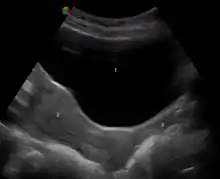

Ultrasonograph depicting urinary bladder at the top, above the uterus to its bottom-left and vagina to its bottom-right

An ultrasound showing the urinary bladder (1), uterus (2), and vagina (3)